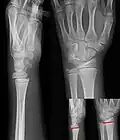

Эпифизеолиз (новолат. epiphyseolysis; эпифиз + др.-греч. λύσις — распад, разрушение) — это травматическое повреждение хрящевой ткани в области соединения метафиза трубчатой кости с эпифизом. Эта зона подвержена травмам преимущественно до окончания периода роста конечностей в длину. У взрослых хрящи в этой области полностью заменены твердой тканью. В медицине болезнь еще называют переломом Салтера — Харриса (Salter — Harris) по двум авторам, описавшим виды патологии. Разрушение хрящевой пластины приводит к асимметрии конечностей, деформации скелета, а иногда и к полному прекращению роста. Источник: https://xnog.ru/meditsina/sustavy/ehpifizeoliz/ Составляет около 15% от общего количества переломов у детей. Почти в половине случаев возникает в области лучезапястного и локтевого суставов. Мальчики страдают вдвое чаще девочек.

Существуют девять типов перелома, 5 из которых описаны Robert B Salter и W Robert Harris в 1963 году[1], остальные, более редкие, описаны позже[2]:

• I тип — поперечный перелом через ростковую зону[3] : 6 % случаев

• II тип — Линия перелома проходит через ростковую зону и метафиз, не затрагивая эпифиз[4]: 75 % случаев

• III тип — Линия перелома проходит через ростковую зону и эпифиз, не затрагивая метафиз[5]: 8 % случаев

• IV тип — Линия перелома проходит через три элемента кости: ростковую зону, метафиз и эпифиз[6]: 10 % случаев

• V тип — Компрессионный перелом ростковой зоны, выглядящий на рентгенограмме в виде уменьшения её высоты (расстояния между эпифизом и диафизом)[7]: 1 % случаев